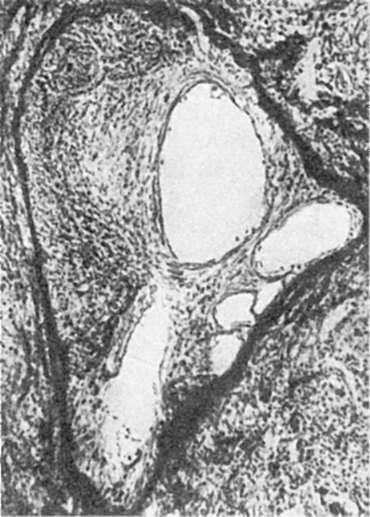

Нейрогуморальная гипертрофия и гиперплазия возникают на почве нарушений функции эндокринных желез (гормональные или коррелятивные гипертрофия и гиперплазия). Физиологическим прототипом таких гипертрофии и гиперплазии, имеющих несомненно приспособительное значение, может служить гипертрофия матки и молочных желез при беременности и лактации. В условиях, когда возникает дисфункция яичников, в слизистой оболочке матки развивается гиперплазия желез, иногда с кистозным расширением их просвета - так называемая железистокистозная гиперплазия эндометрия (рис. 88),

сопровождающаяся нерегу-

Рис.

88. Железистокистозная гиперплазия эндометрия

лярными маточными кровотечениями. При атрофических процессах в яичках в грудной железе мужчин развивается гиперплазия железистых долек, что приводит к увеличению размеров всей железы - отмечаетсягинекомастия (от греч. gyne - женщина, matos - грудь). Гиперфункция передней доли гипофиза, возникающая обычно на почве аденомы, сопровождается увеличением органов и выступающих частей скелета - развиваетсяакромегалия (от греч. akros - крайний, выступающий, megalos - крупный). Коррелятивные гипертрофии и гиперплазии, возникающие как реакция на те или иные гормонально-обусловленные стимулы, нередко являются почвой для опухолевого процесса.